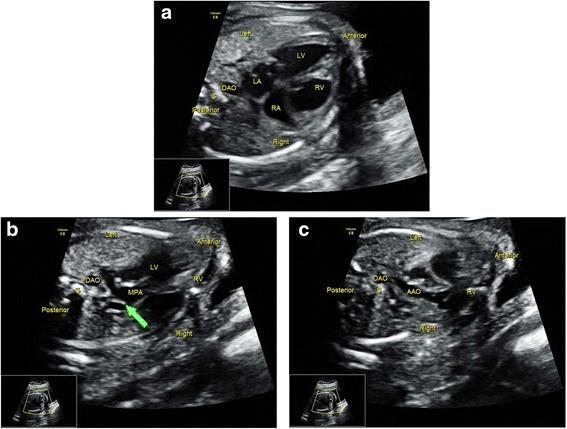

Prenatal cardiac screening is of great importance as it contributes to appropriate neonatal management and helps parents to make a decision regarding their pregnancy. The aim of our study was to evaluate the efficiency of a newly proposed screening protocol in the detection of fetal congenital heart disease (CHD).

This was a prospective study. A total of 52 cases of confirmed CHD fetuses and 248 cases of randomly selected normal fetuses were included in the study. Two sonographers with similar experience performed the cardiac screenings under two different protocols independently. The conventional protocol (Protocol A) paid greater attention to the four-chamber view and the outflow tract views. A 6-month training program was provided to sonographers performing scans under the new protocol (Protocol B), which emphasized systematically evaluating fetal cardiac anatomy and hemodynamics. Color Doppler was mandatory and some ultrasonic signs for special cardiac anomalies were also introduced into this protocol.

Protocol B detected more cardiac anomalies than did Protocol A (96.2 % vs. 61.5 %, P < 0.01). Specifically, Protocol B was superior to Protocol A in detecting cardiac malpositions, abnormal systemic and pulmonary venous connection, right aortic arch, transposition of the great arteries, and congenital corrected transposition of the great arteries. By visualizing flow disturbance and retrograde flow with color Doppler, Protocol B was better than Protocol A in screening valvular associated malformations, such as pulmonary atresia, pulmonary stenosis, tricuspid dysplasia, etc. For the normal fetuses, Protocol B was better than Protocol A in reducing the false-positive detection of septal defects.

The current study introduces an enhanced protocol for fetal cardiac screening, under which the obstetric screening sonographers systematically identify fetal cardiac anatomy and hemodynamics. A short-term training program makes it possible for the screening sonographers to become familiar with the new protocol, and its value has been confirmed due to improvements made in screening efficiency.